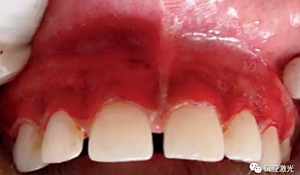

術(shù)后即刻

患者術(shù)后無明顯疼痛不適,沒有出現(xiàn)大量出血、感染或結(jié)痂現(xiàn)象。整個(gè)恢復(fù)過程較為順利?;颊呓邮芏雀?,治療效果明顯。